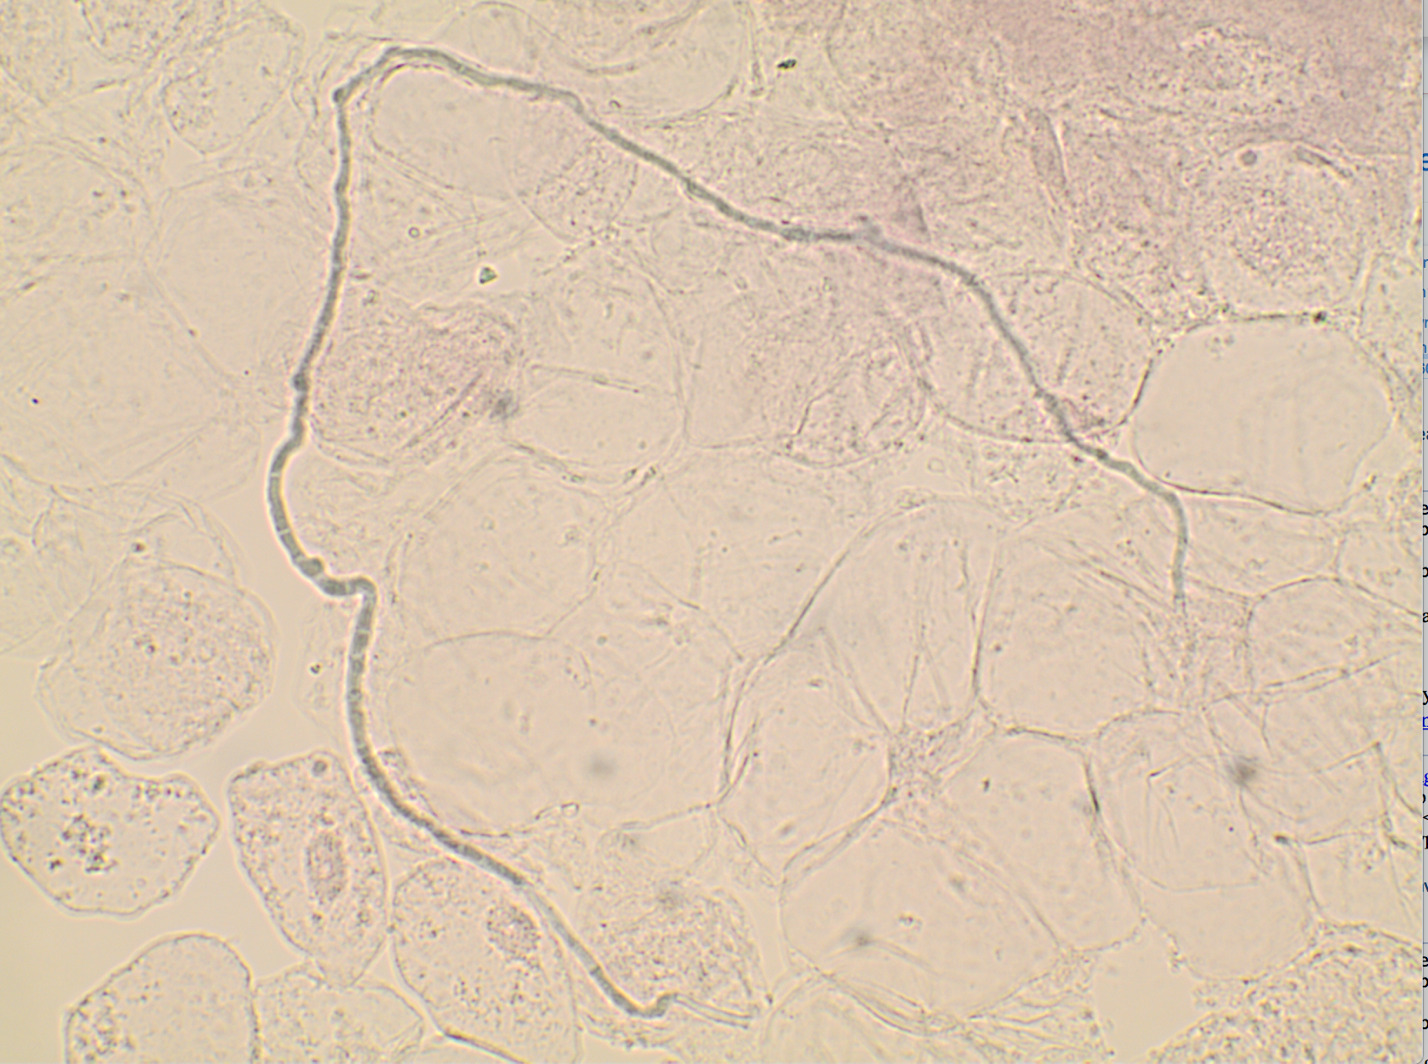

Tinea corporis was suspected. A potassium hydroxide preparation from the advancing, scaled border of the patch demonstrated septate hyphae confirming the diagnosis of tinea corporis (Image 2). The previous topical treatments were discontinued, and ketoconazole 2% cream was applied twice daily for one month. Excellent clearing was noted. The ketoconazole 2% cream was continued once weekly for 6 weeks to ensure the condition did not recur.

When tinea is suspected, superficial skin “scraping” with a rounded #15 or #10 blade or curette will produce scale for immediate examination with KOH 10% solution or inked KOH solution (Chicago Blue or chlorazole black E).5 The more scale obtained, the higher is the likelihood of identifying hyphal elements when present. The presence of septate hyphae confirms the diagnosis (Image 2).1 When materials for a KOH are unavailable, scale can be submitted in a clean container for polymerase chain reaction (PCR) which can be resulted in several days or a fungal culture which takes 3-4 weeks. False negatives may occur. If a strong concern for tinea exists, a PCR or fungal culture should still be obtained. In contrast to topical steroids, empiric therapy with antifungals may be used while awaiting confirmation, as it would be unlikely aggravate other dermatoses.